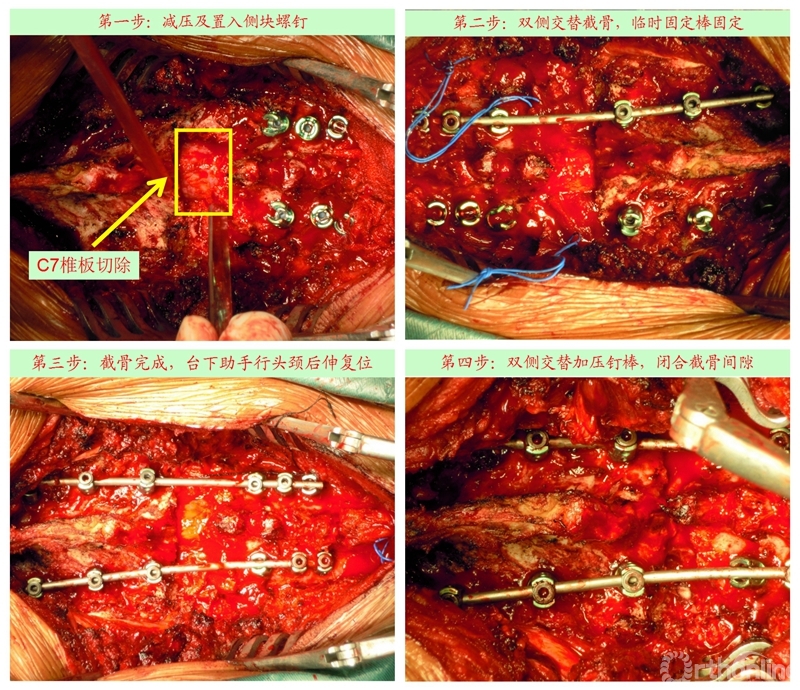

手术步骤

众所周知,脊椎结核后突畸形是结核病严重的后遗症之一。不仅影响患者外表仪容和心理,还可能出现晚发病灶造成截瘫。30多岁的小李就是一位脊柱结核后造成后凸畸形伴截瘫的患者,其畸形角度高达90度。针对此类患者的治疗大多就是截骨矫形,手术创伤大不说,椎体切除后造成的脊柱失稳等一系列后遗症也是令医生和患者担忧的。为解决临床上的这类问题,丁文元教授对传统的PVCR截骨技术进行了简化和改良,即后路单侧截骨部分椎体切除固定矫形术(UPVCR)入路,该技术采用后方单侧截骨,切除部分椎体、相邻椎间盘大部,保留对侧椎弓根及部分椎体,重建置入钛网支撑。随后,丁文元教授通过UPVCR技术对小李实施了手术,经过家人悉心地照顾,小李术后肌力恢复的良好,很快就出院了。三个月复查时竟是自己走路来的,临床疗效让患者及家人很是满意。

丁文元教授介绍说,UPVCR技术的优势在于手术操作简单,易于掌握,学习曲线短,手术时间短,出血少,神经并发症少;临床应用时极少发生断钉、断棒、不融合的现象,术中保留了良好的血运、植骨床,提供骨生长环境,保证部分骨支撑,术后极少发生矫正丢失,临床效果肯定。